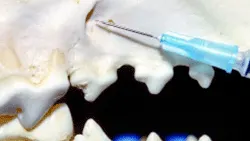

Step-by-Step: Inferior Alveolar (Mandibular) Nerve Block

The mandibular nerve block affects the bone, teeth, soft tissue, and tongue on the infiltrated side.

1. In dogs, there is a palpable notch on the caudal ventral mandible just cranial to the angular process. If the notch cannot be palpated, select the point on the ventral mandible that is located on a vertical plane with the lateral canthus.

2. Using this landmark, insert the needle at the lingual aspect of the ventral mandible.

3. Advance the needle to the midpoint between the ventral and dorsal borders of the mandible.

4. Aspirate and slowly inject.

A close-up view of a canine skull with a syringe positioned near the mandible, illustrating a veterinary procedure for administering an injection. The focus is on the anatomical landmarks relevant for safe injection techniques in veterinary practice.